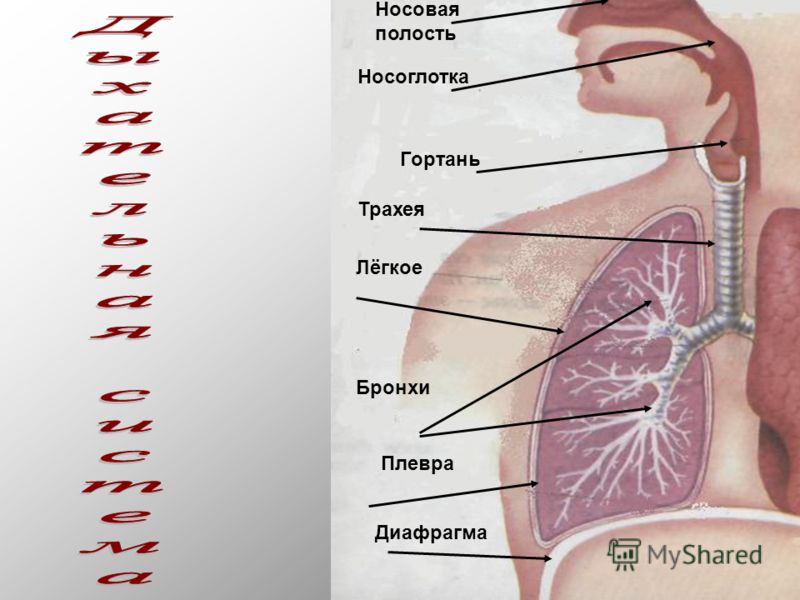

Еда для Легких и Бронхов - Полезные Рецепты